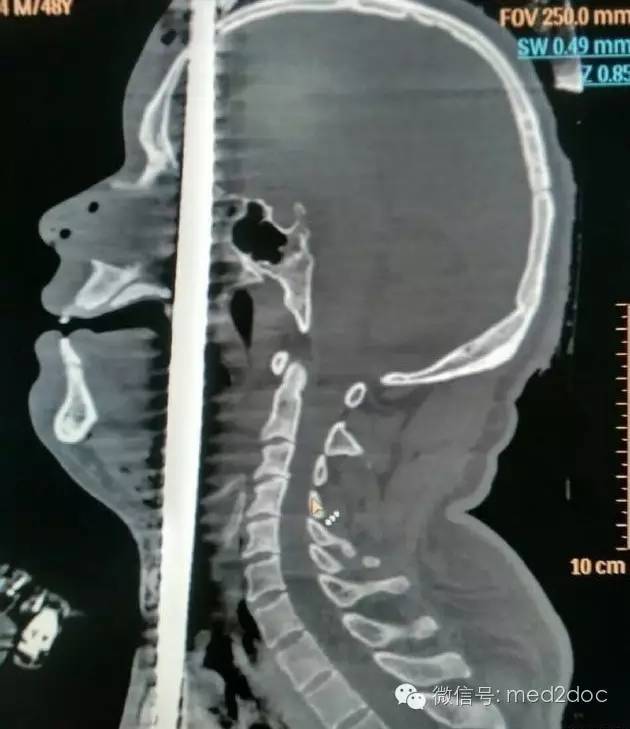

经过CT等全方面检查后,确定钢筋已贯串男子的泌尿、腹部、胸部、口腔、鼻腔、脑部等具体部位。钢筋从男子的右阴囊插入,途径泌尿系统,伤及腹部的肝脏,紧贴颈动脉贯串而过。从咽喉直插入口腔,伤及舌头,从上颚经鼻腔,插入大脑,钢筋从头顶穿出。